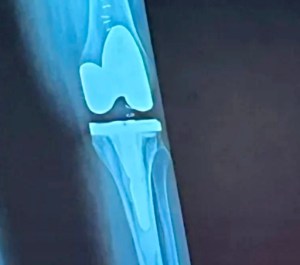

Getting a total knee replacement was the best upgrade I’ve ever made. I went from a creaky antique knee to a high-performance model in just a few hours.

Fast forward to my new bionic knee, and now I’m living my best life. I still have to build more strength but now I can chase after toddlers, conquer grocery aisles like a pro, and take the family dog on walks that both the pet and I actually enjoy. The cardio walks and bike rides I can take since surgery have even helped me shed about 30 pounds in the past few months.

So yes, total knee replacement might sound daunting — but for me, it was the ultimate reboot. If you are suffering in pain and need joint replacement surgery I recommend not putting it off too long. I traded pain for possibility, stiffness for spontaneity, and now I’m walking proof that sometimes the best way forward is with a brand new knee.